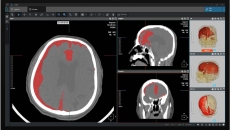

They will deploy AI to help reduce delays and gaps in stroke care management.